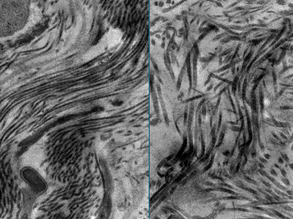

Muscling In